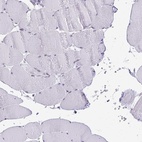

Immunohistochemistry analysis in human pancreas and skeletal muscle tissues using Anti-PLA2G1B antibody. Corresponding PLA2G1B RNA-seq data are presented for the same tissues.